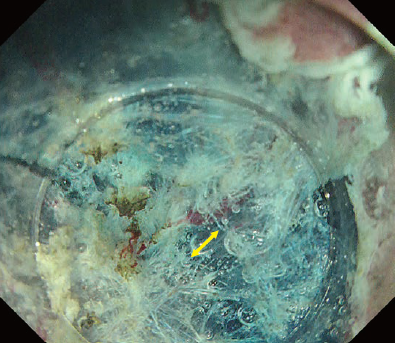

In cases with fibrosis, the knife’s jet function is particularly useful. Fig. 10 shows a mid-procedure phase in which the fibrotic region has been exposed by digging on both sides. Because secure preservation of the dissection space is desirable at this stage, the usual approach is to switch devices and insert a local injection needle. However, changing devices takes time, and it is not uncommon for the field of view to change during that interval. Instead, using the DualKnife J’s jet function allows you to proceed rapidly with dissection while delivering fluid.

When local injection is performed with a needle, the submucosal cushion may dissipate when the device is switched to the knife. The jet function, on the other hand, makes it possible to start dissection at the exact moment the submucosal layer is elevated.

The procedure to use the jet function is simple: 1) Retract the tip; 2) Lightly touch the target area with the sheath tip to deliver the liquid press the coagulation wave pedal on the electrosurgical unit; 3) Project the knife tip; 4) Start the jet function through the knife.

This enables effective elevation of the submucosal layer. Efficient delivery is also possible by connecting a water-jet pump to the knife. If delivering saline, you can attach a 5–10 cc syringe externally to the knife and push by hand (Fig. 11).